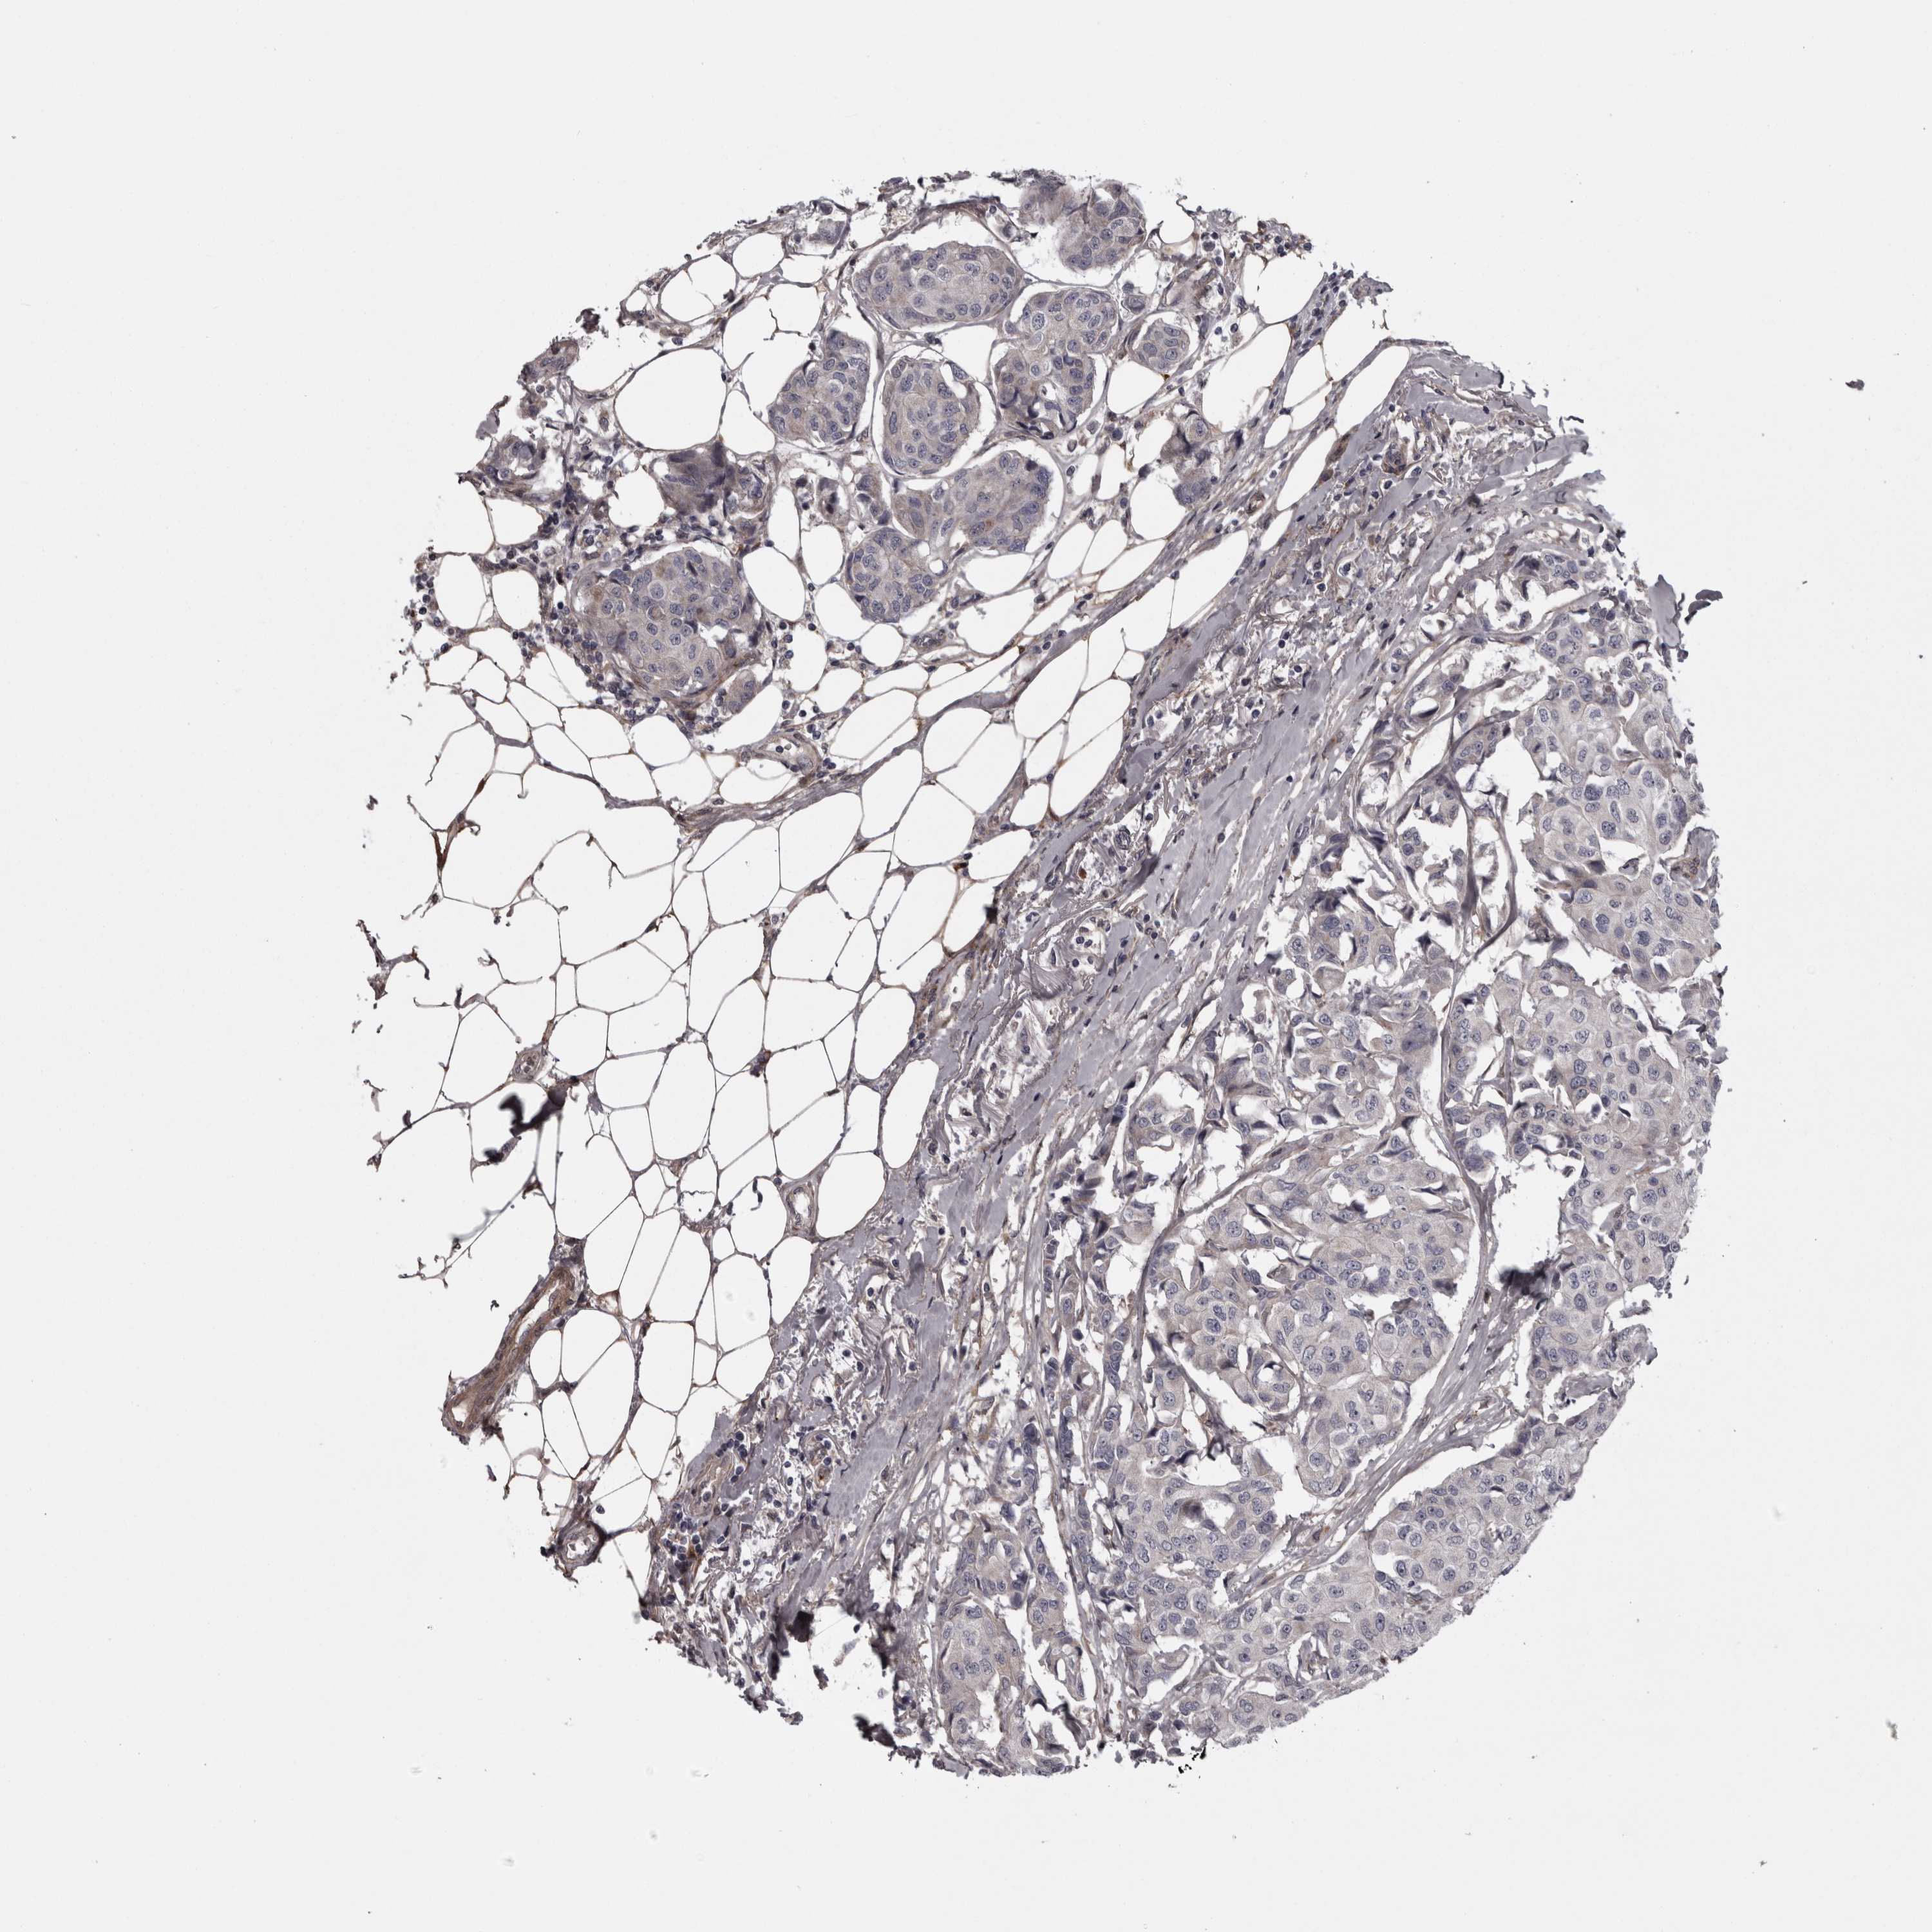

CANCER BREAST CANCER Show tissue menu

BRCA TCGA BRCA VALIDATION PROTEIN EXPRESSION